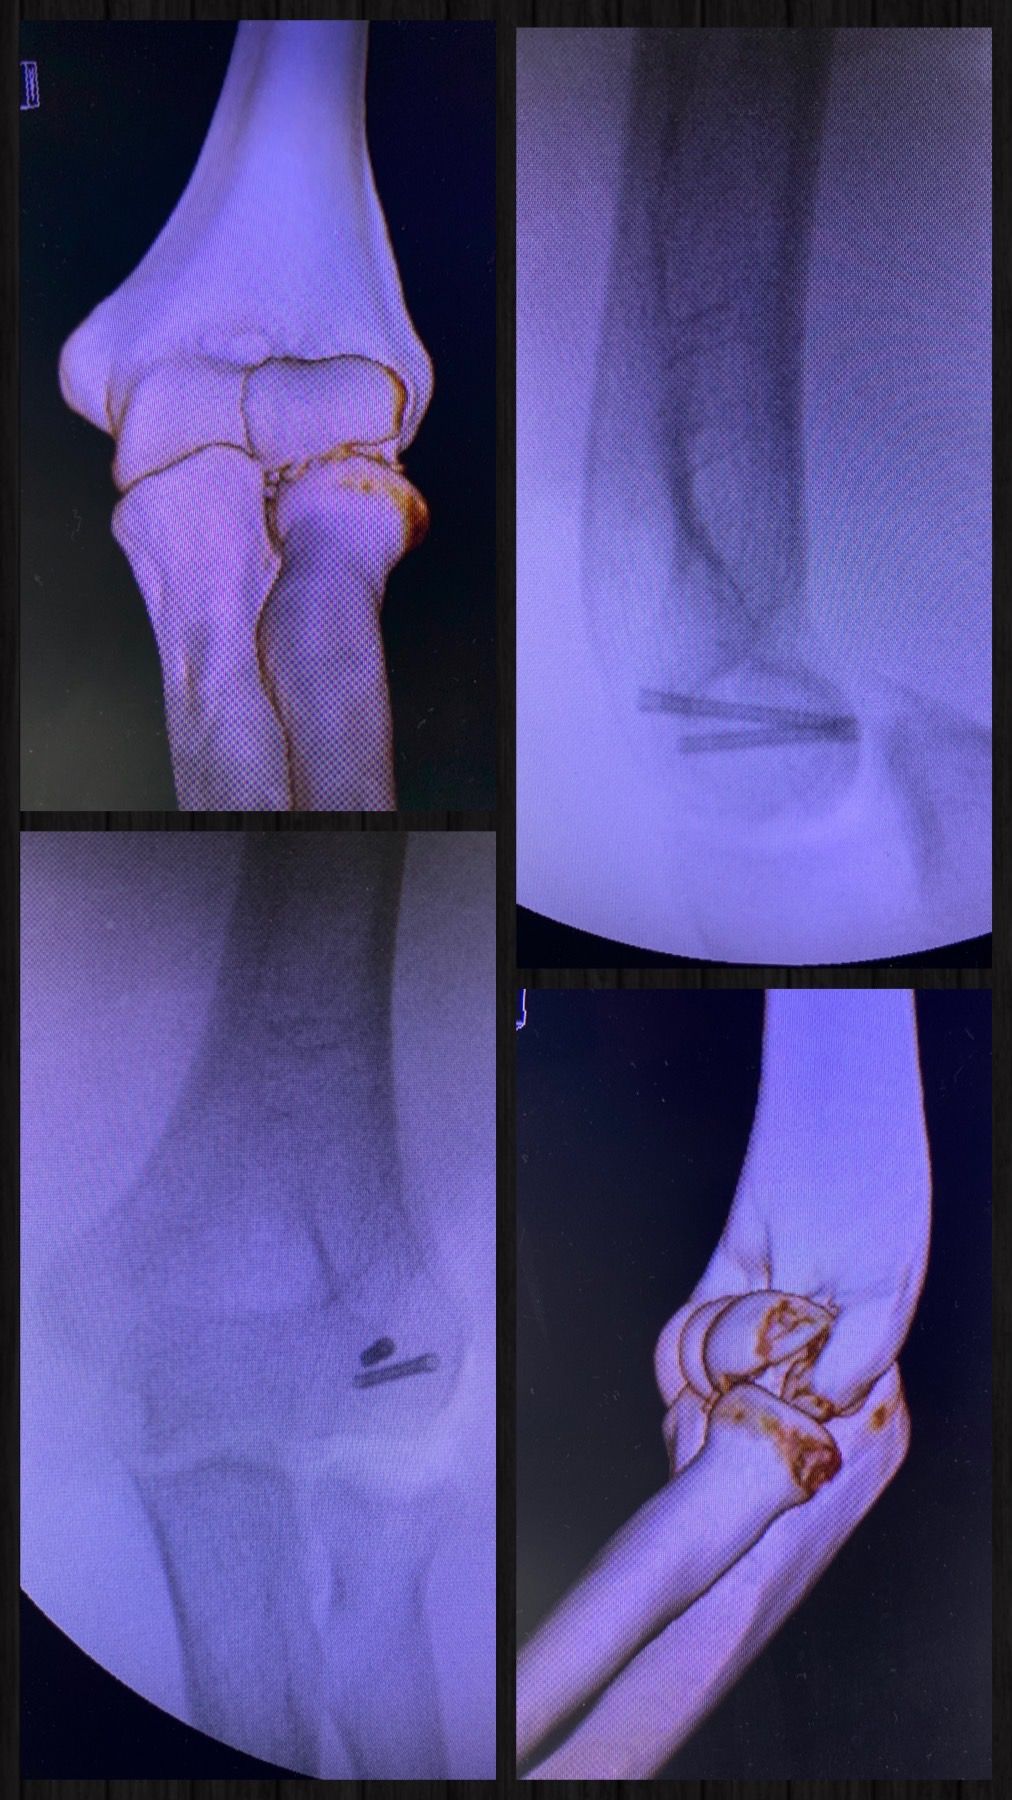

Se especializa en Síndrome del Manguito Rotador, Artroscopía de Hombro, Luxación de Hombro, Epicondilitis Lateral (Codo de Tenista), Fractura de Clavícula, Disyunción Acromioclavicular, Fracturas de Codo.

Conferencista. Tríada Terrible del Codo. II Jornadas de Traumatología. Hospital Universitario de Caracas (HUC). Caracas, Venezuela. 2015